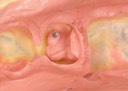

Mark Chun #2 & 3 caries removal

Mark Chun #2 & 3 prep